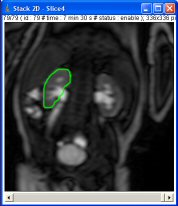

Draw a ROI on the dynamic stack with the ImageJ tools (freehand ROI is strongly recommended). This ROI must be limited to the parenchyma (cortex and medulla – excluding excretory system and fat). You can see an example on the following image. It may be necessary to register the images with use of a ROI during the 4 first minutes due to breathing motion of the kidney, especially in adults (use the registration tab).

Then, click on the “Graph” button to get the graph window. Be careful, the curve is normalized (see excretion tab).